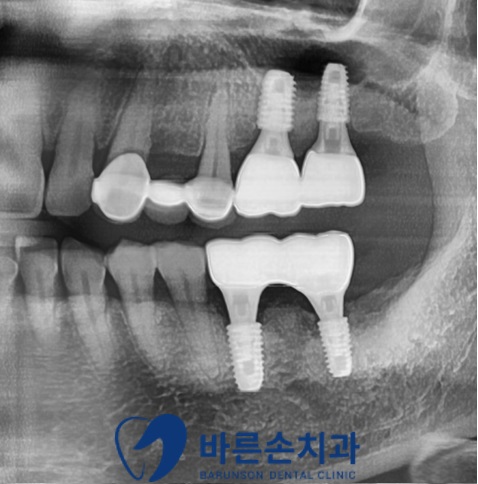

2~3달 후,

이식한 뼈와 임플란트가 잘 자리 잡았고,

임플란트 고정력이 충분히 나와

상부 크라운을 제작해 마무리하였습니다.

위 환자분은 다행히 최소 기간만 기다린 후 보철을 올리게 되었고,

흔들리는 치아 없이 튼튼한 임플란트로 잘 식사하실 수 있다며 만족하시고 계십니다^^